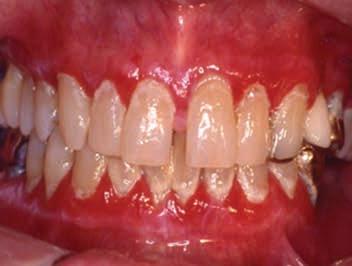

Oral manifestations of pemphigus vulgaris include bullous lesions, erosions with ragged borders, desquamative gingivitis and a positive Nikolsky’s sign (Figures 7,8). Multiple large lesions on the skin can result in fluid loss, electrolyte imbalance, septicemia, and death.

Figure 6. Symblepharon (scar) in a patient with MMP extending from the conjunctiva to the eyeball. Figures 7 and 8. Erosions with ragged borders seen with pemphigus vulgaris. Figure 7 Figure 8